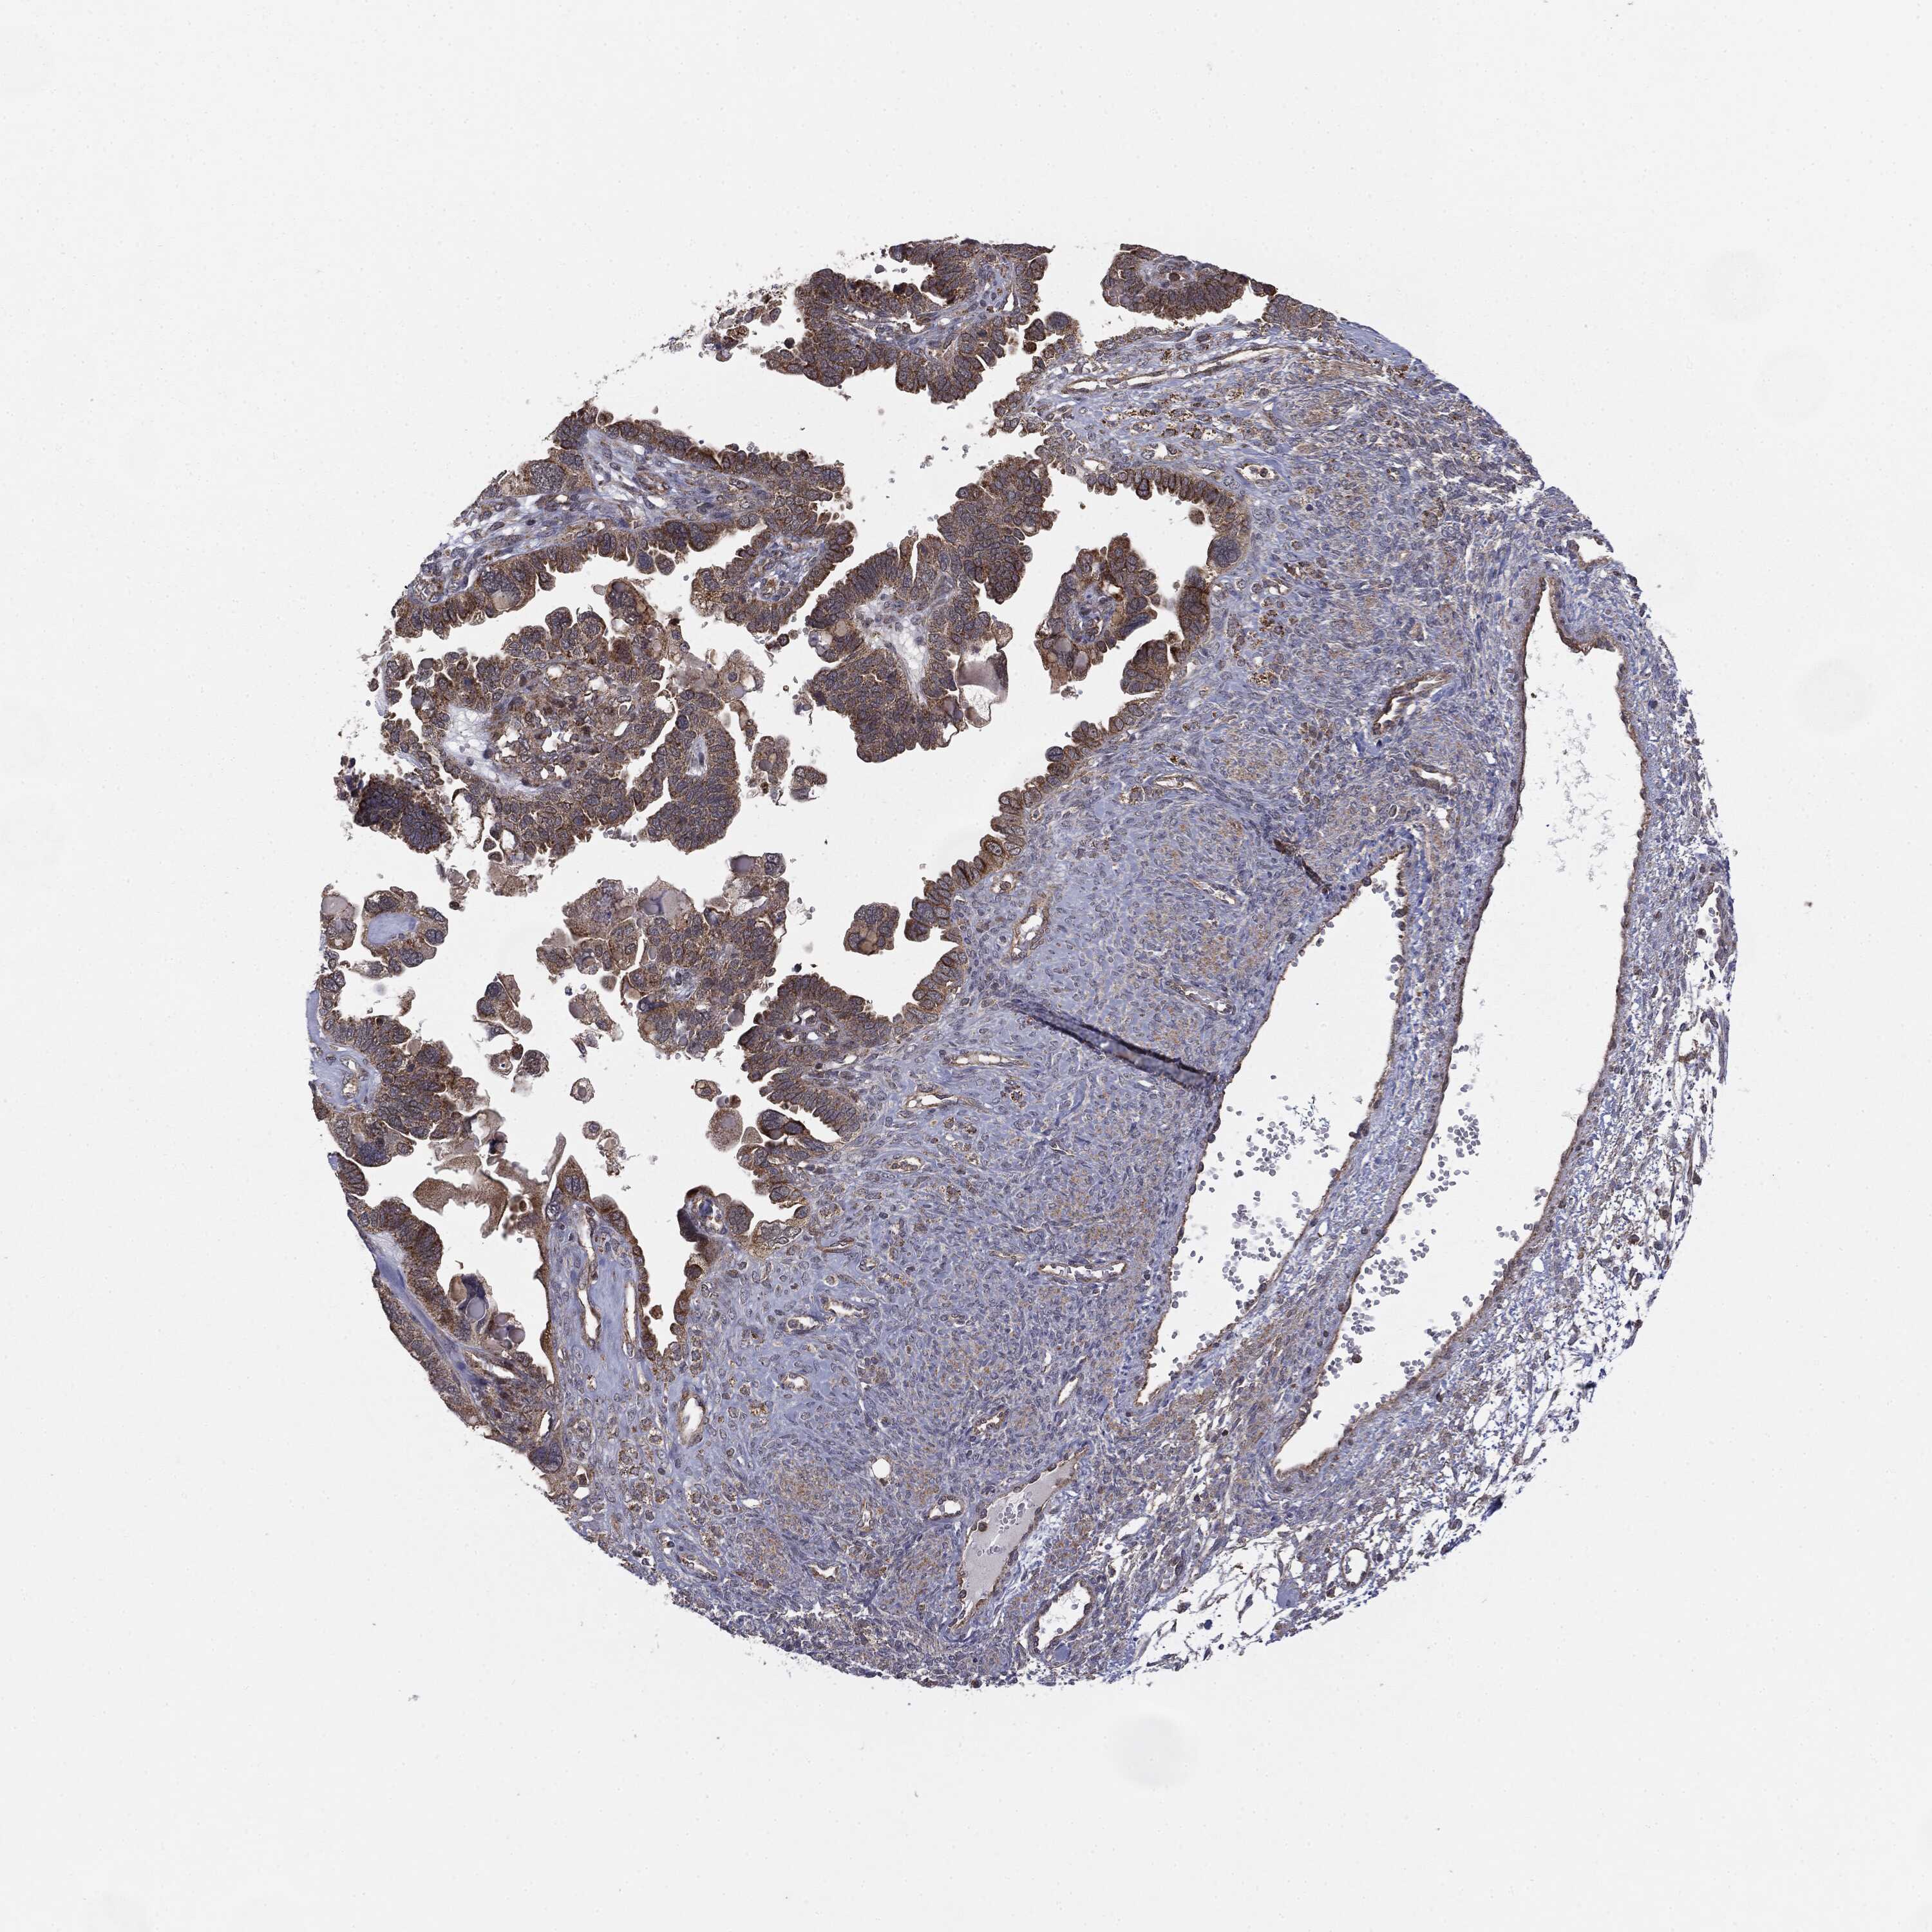

OVARIAN CANCER - Protein expressioni

A mouse-over function shows sample information and annotation data. Click on an image to view it in a full screen mode. Samples can be filtered based on level of antibody staining by selecting one or several of the following categories: high, medium, low and not detected. The assay and annotation is described here.

Note that samples used for immunohistochemistry by the Human Protein Atlas do not correspond to samples in the TCGA dataset.

Antibody stainingi

Antibody staining in the annotated cell types in the current human tissue is reported as not detected, low, medium, or high, based on conventional immunohistochemistry profiling in selected tissues. This score is based on the combination of the staining intensity and fraction of stained cells.

Each image is clickable and will lead to virtual microscopy that enables deeper exploration of all samples and also displays staining intensity scores, fraction scores and subcellular localization as well as patient and tissue information for each sample.

CAB069425

Cystadenocarcinoma, mucinous, NOS